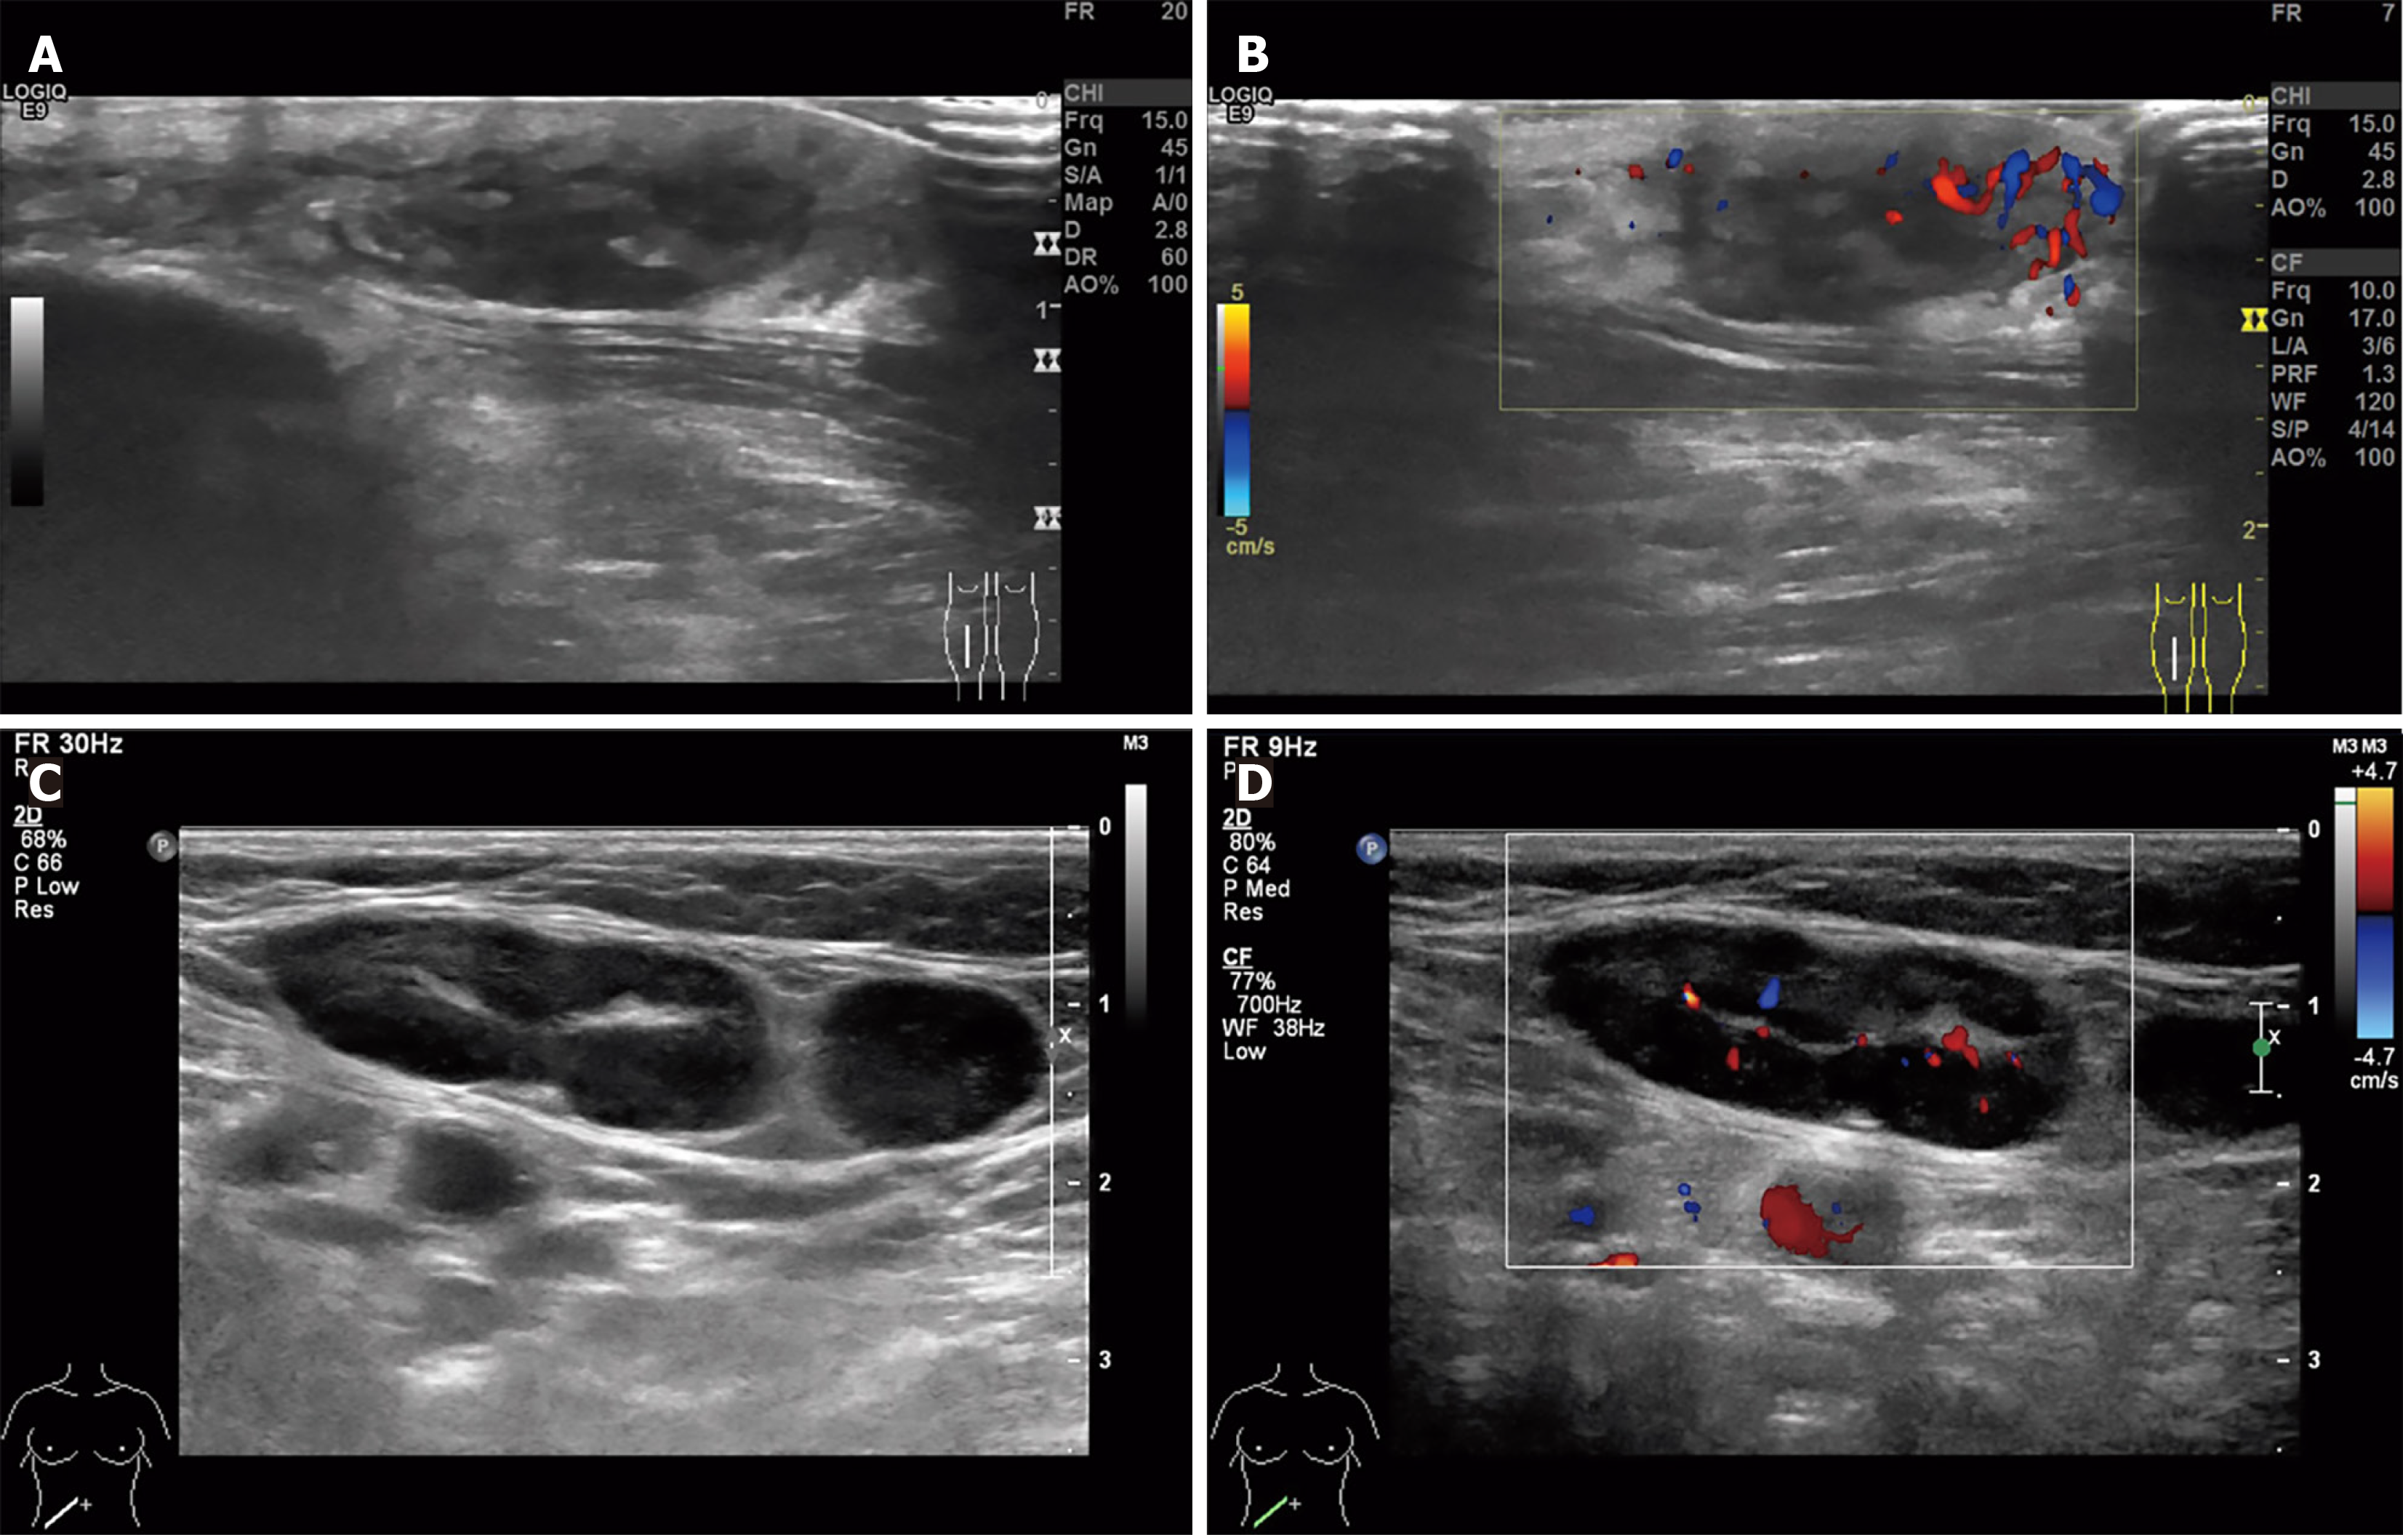

Figure 2 Ultrasound imaging of the right lower leg mass and right inguinal lymph nodes.

A: A hypoechoic subcutaneous mass (25 mm × 9 mm × 25 mm) in the mid-right lower leg, exhibiting irregular margins and an ill-defined shape; B: The adjacent tissue demonstrates increased echogenicity, accompanied by prominent peripheral vascularity; C: Multiple enlarged lymph nodes are observed in the right inguinal region, with the largest measuring 30 mm × 13 mm and showing asymmetrical cortical thickening; D: Intranodal blood flow appears as punctate/Linear vascular signals.